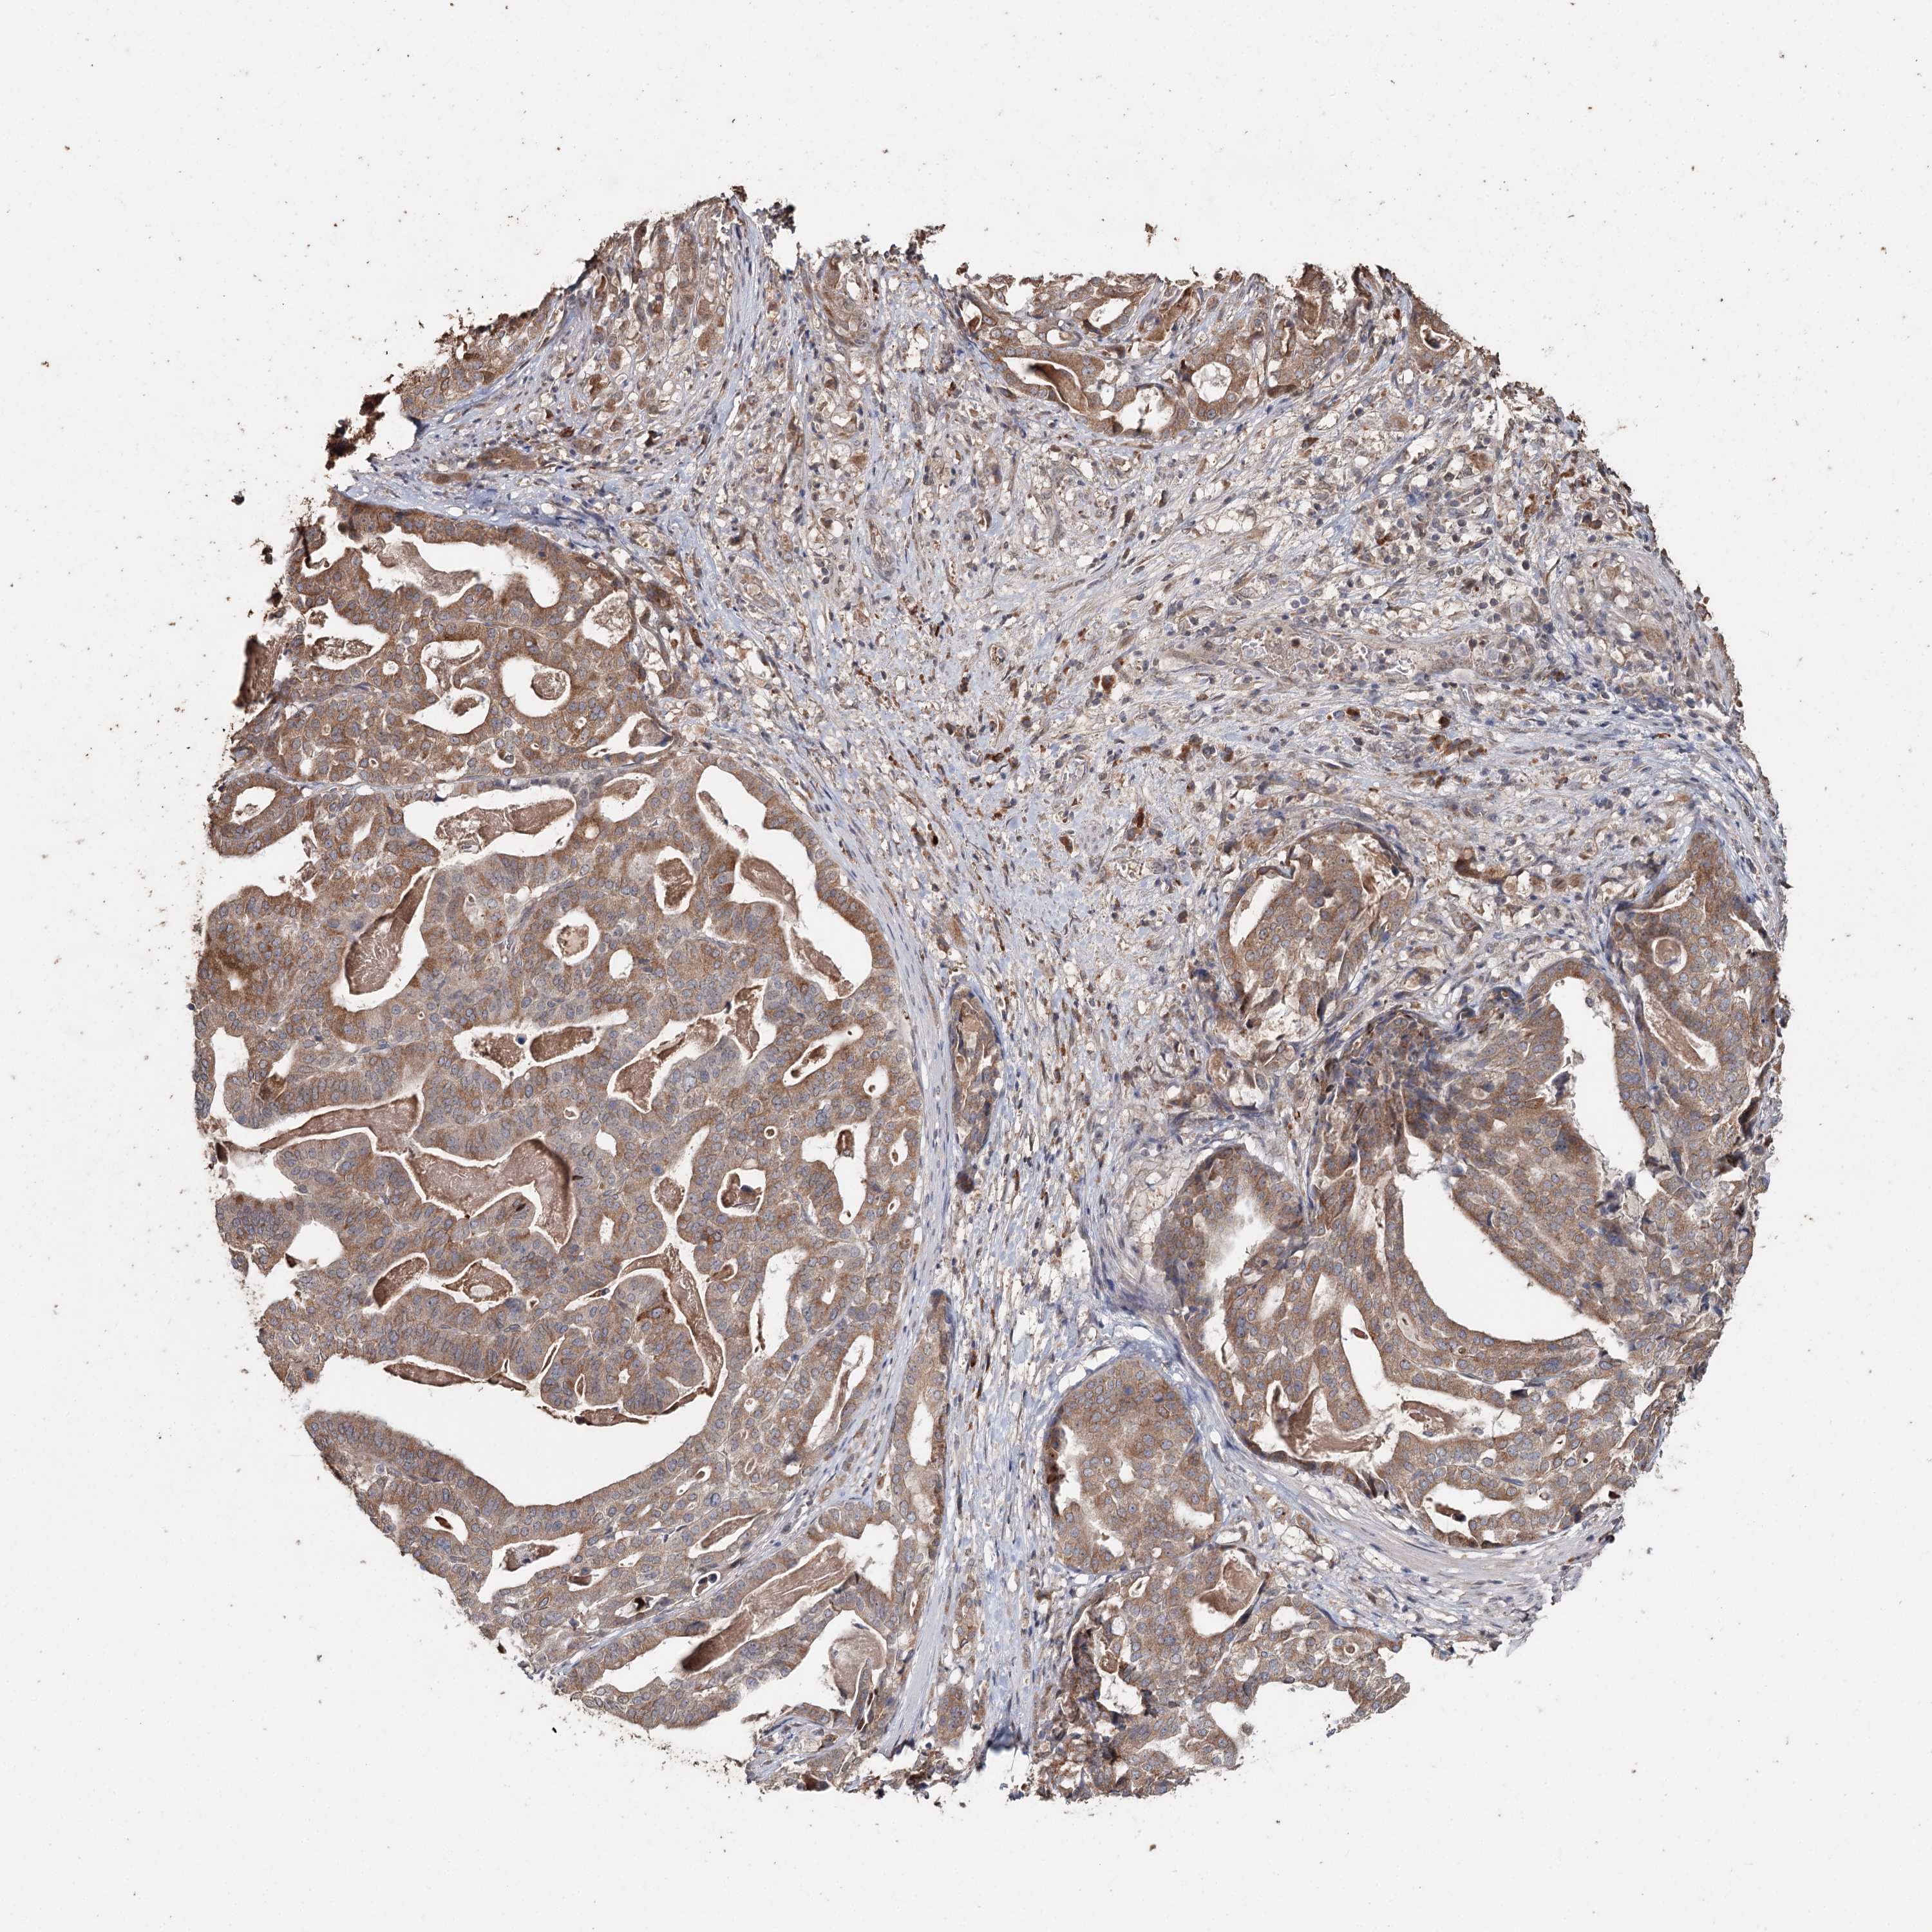

STOMACH CANCER - Protein expressioni

A mouse-over function shows sample information and annotation data. Click on an image to view it in a full screen mode. Samples can be filtered based on level of antibody staining by selecting one or several of the following categories: high, medium, low and not detected. The assay and annotation is described here.

Note that samples used for immunohistochemistry by the Human Protein Atlas do not correspond to samples in the TCGA dataset.

Antibody stainingi

Antibody staining in the annotated cell types in the current human tissue is reported as not detected, low, medium, or high, based on conventional immunohistochemistry profiling in selected tissues. This score is based on the combination of the staining intensity and fraction of stained cells.

Each image is clickable and will lead to virtual microscopy that enables deeper exploration of all samples and also displays staining intensity scores, fraction scores and subcellular localization as well as patient and tissue information for each sample.

Antibody HPA005480

Antibody HPA024300

Antibody CAB037030

Staining

High

Medium

Low

Not detected

Intensity

Strong

Moderate

Weak

Negative

Quantity

>75%

75%-25%

<25%

None

Location

Nuclear

Cytoplasmic/membranous

Cytoplasmic/membranous,nuclear

Adenocarcinoma, NOS

Adenocarcinoma, High grade